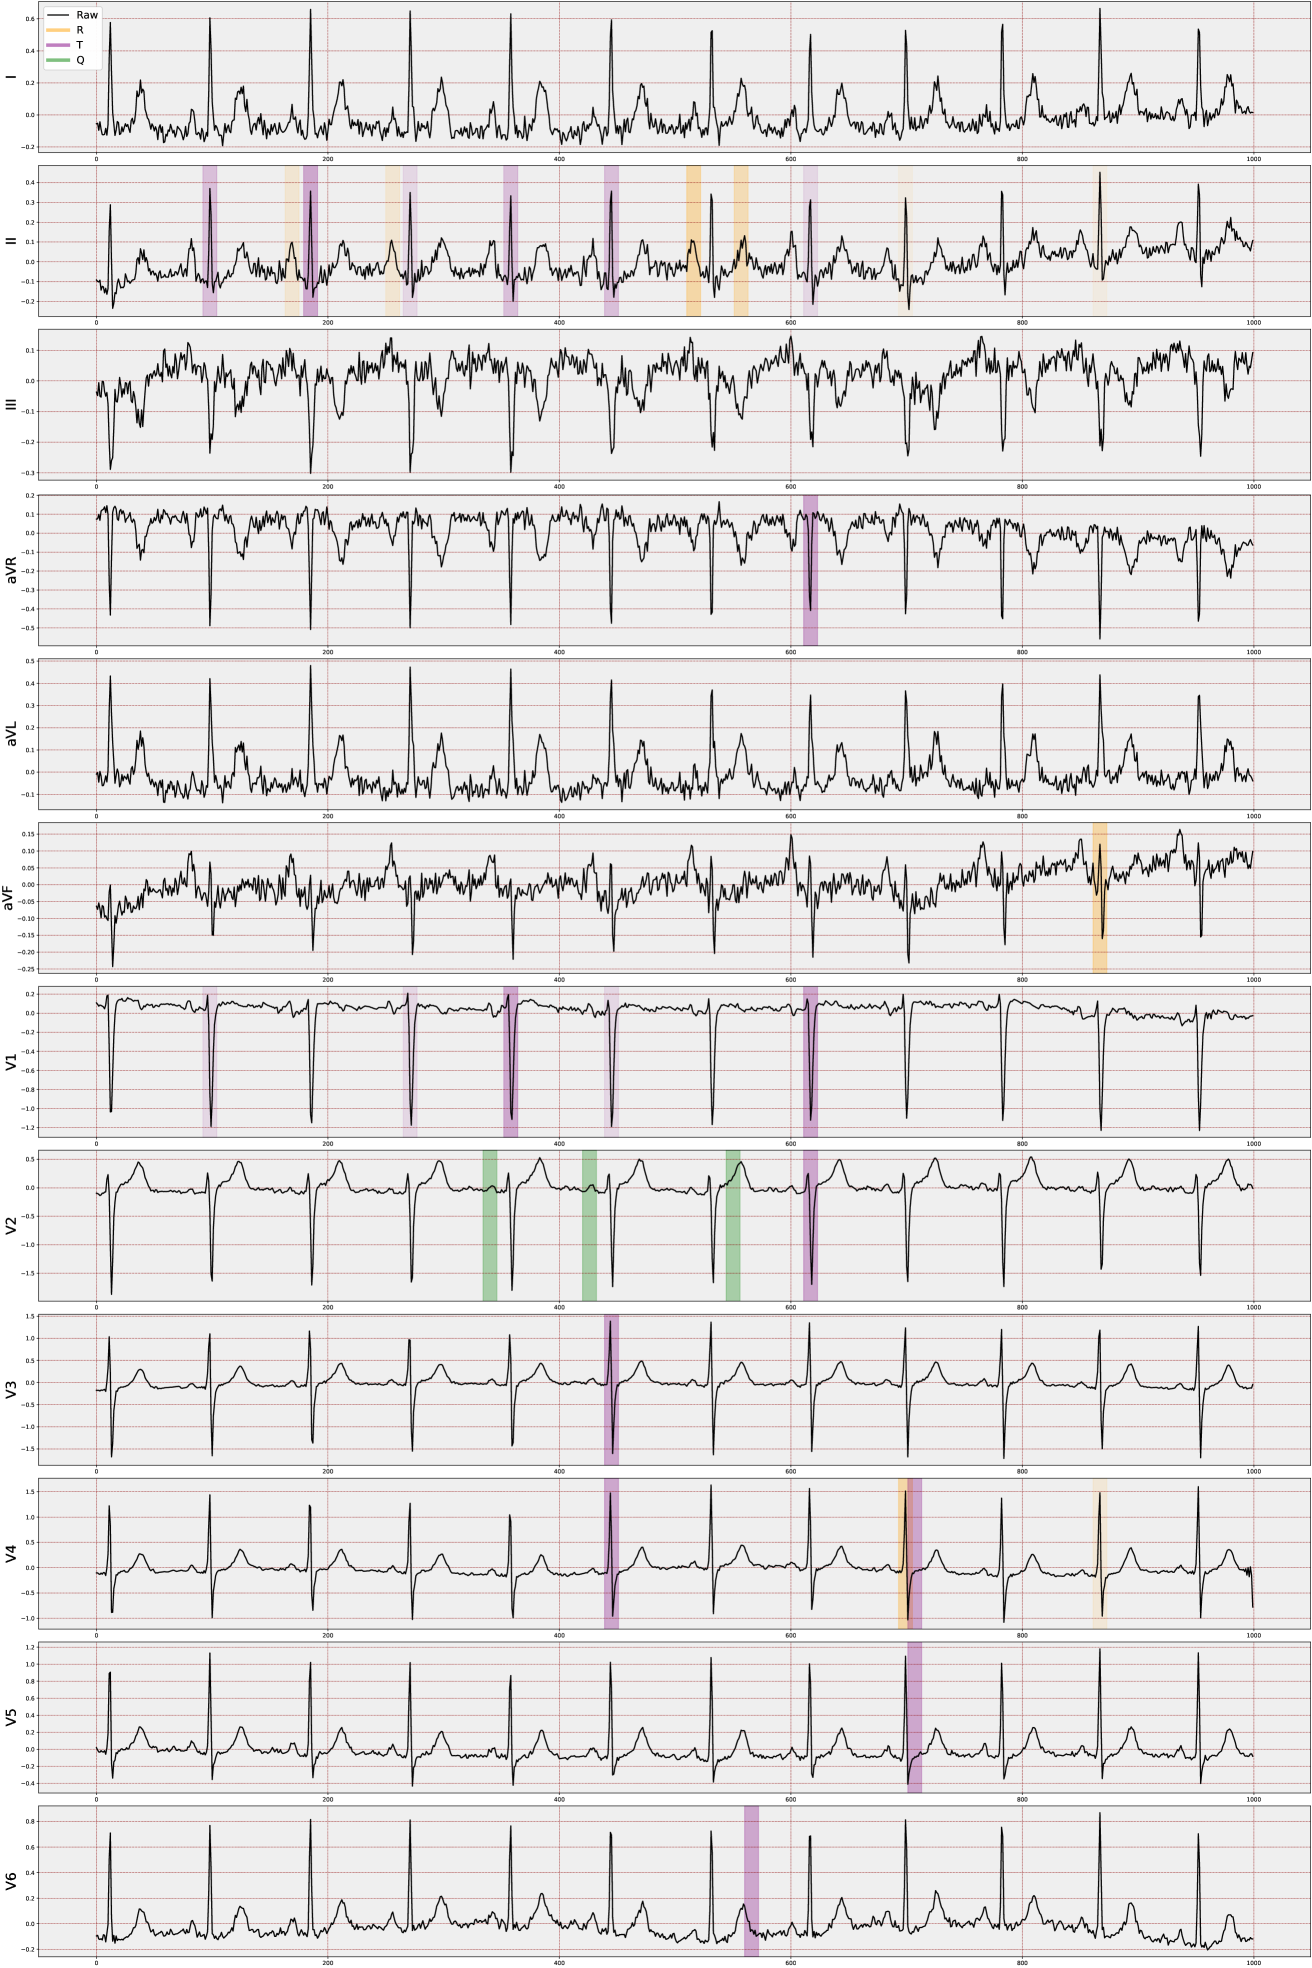

We have developed VCCE (Algorithm 1), a method to improve the presentation of counterfactual clues in ECG reports for clinicians. This method integrates counterfactual data with extracted ECG features, emphasizing significant waveform features (PQRST) and highlighting their diagnostic implications. VCCE employs a dynamic visualization approach, adapting to various counterfactual scenarios and their impacts on ECG waveforms.

For visualization, VCCE offers options to display peaks (such as the R peak) and chosen amplitude features (like II_R), as identified by the counterfactual algorithm, in selected regions. Advanced features (for example, V3_ST), which are calculated based on amplitude differences between two peaks, are represented as lines with their distance values overlaid on the ECG signal (refer to Supplementary Figure C.7). Additionally, in the visualization of counterfactuals, the frequency with which a particular amplitude feature is chosen in an alternative scenario directly influences its prominence in the ECG report. The more often a feature is selected, the more distinctly it is highlighted.

This approach, color=red!80]R2.17adaptable beyond the specific ECG task, allows us to observe changes in the PQRST complex across multiple "possible worlds," offering a way to perceive alterations across various scenarios. The primary rationale for assuming the applicability of a VCCE-like approach across a range of ECG tasks lies in the nature of the ECG features employed, which are similar to those used in other ECG-dependent cardiac conditions. These features are extracted based on the structure of the P-, Q-, R-, S-, and T-waveforms (cardiac cycle) at the beat level, a consistent factor across all ECGs. The key advantage is that these derived features provide distinct temporal and amplitude-level information that is inherently interpretable. As a result, we can not only numerically analyze the generated counterfactual scenarios but also visually assess their impact on specific waves within particular leads and beats.

color=red!80]R2.6In the proposed study, we note that the selected top 20 features are predominantly time independent due to their dependence on lead-wise amplitude characteristics across all MI cases in the dataset, with RR_Next being the only temporal one. Therefore, our visualization method primarily focuses on amplitude-based (non-temporal) features. Additionally, we have included four more features (V2_T, V3_T, V4_T, and V6_T), selected by domain experts, to enhance individual resolution, such as distinguishing between inferior and anterior case differences. Consequently, we initiate a decoding process to unfold the temporally compressed beats. This decoding involves expanding the feature names to indicate the specific area influenced by the counterfactuals responsible for the change, encompassing details such as the lead, the waveform feature, and the beat associated with the counterfactual’s impact. This way, we are individually marking the features that contribute the most significant distinction between the two diagnoses.